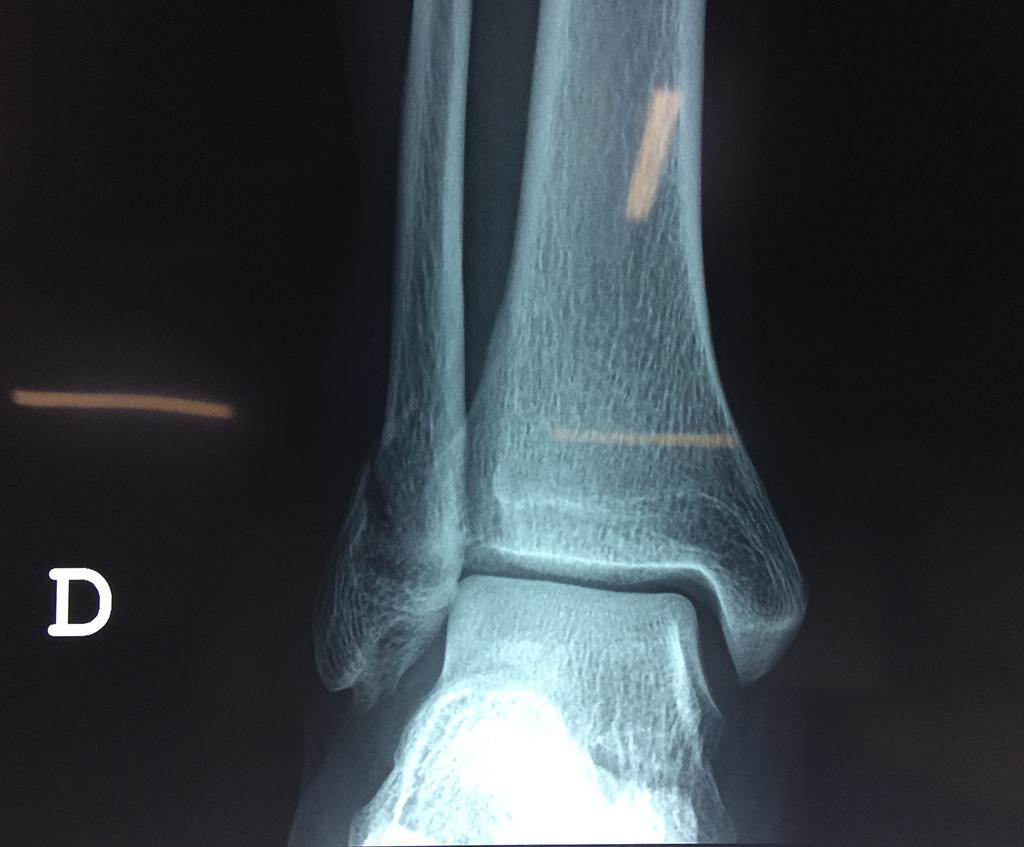

Una fractura de tobillo es la rotura de uno o más de los huesos del tobillo. Estas fracturas pueden ser:

Cuando se necesita cirugía, es probable que esta implique el uso de clavijas de metal, tornillos o placas para sostener los huesos en su lugar mientras la fractura se consolida. Los elementos de soporte pueden ser temporales o permanentes.